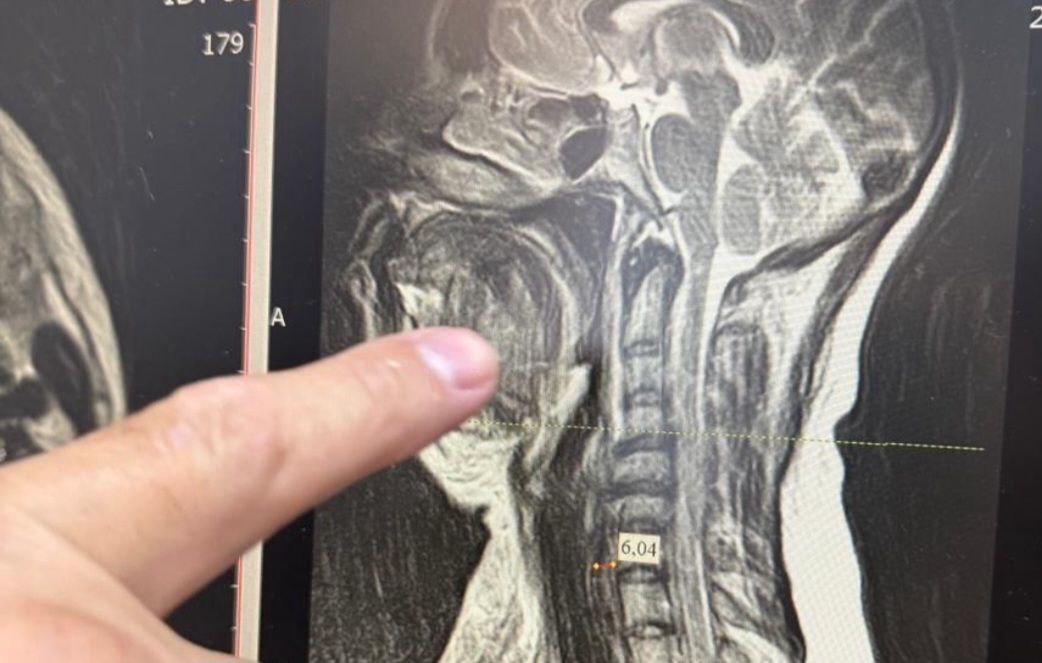

Врачи столкнулись с сложным диагнозом — двусторонней флегмоной окологлоточного пространства. Если вовремя не приступить к лечению этого заболевания, последствия могут привести к летальному исходу.

Из-за сильного отёка шейных тканей медикам пришлось работать через трахею. Челюстно-лицевой хирург Шахбан Мисриев установил около восьми дренажей. Три дня пациентка провела в реанимационном отделении, подключённой к аппарату ИВЛ.